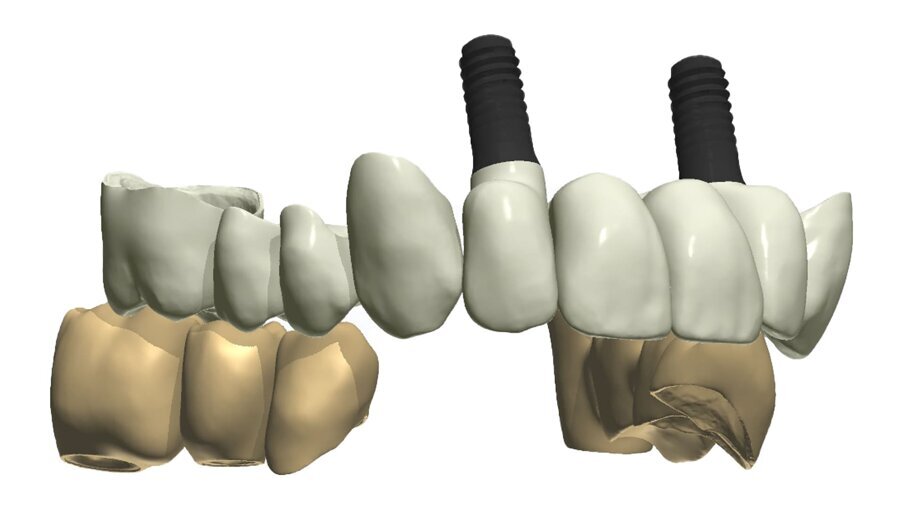

Fig. 35_Sovrapposizione di un’immagine stilizzata degli elementi realizzabili con un margine muso ricreato.

Fig. 36_Wax-up digitale funzionalizzato per entrambe le arcate in visione frontale.

Fig. 37_La medesima immagine viene sottratta dagli elementi di supporto. Tale visione consente di evidenziare i margini coronali, di valutare i movimenti masticatori, gli svincoli coronali le conformazioni anatomiche ottimizzando le singole funzioni.

Fig. 38_Il ponte tra gli impianti in Zirconia rappresenta un progetto complesso tra il rispetto del tunnel mucoso, l’anatomia vestibolare, gli spazi circolari e il foro per l’avvitamento coronale.

I dati raccolti sono molti ma la procedura digitale consente di sommarli e confrontarli senza limiti e indicando le possibili migliori e correzioni lungo il percorso. Dopo un breve periodo di condizionamento dei tessuti (Fig. 30) rileviamo l’impronta master per la finalizzazione ultima della riabilitazione protesica. L’impronta degli elementi naturali viene rilevata posizionando dei fili detrattori secondo la tecnica del doppio filo mentre per gli impianti verranno usati gli scan body dedicati (Fig. 31). Le potenzialità digitali consentiranno di avere una stabile lettura della posizione di centrica rilevandola prima della rimozione dei provvisori e sovrapponendola a provvisori rimossi (Fig. 32). In laboratorio l’odontotecnico realizza i modelli (Figg. 33, 34) sovrappone le immagini (Fig. 35) e raccoglie gli elaborati dei vari passaggi che porteranno alla finalizzazione del progetto digitale (Figg. 36, 37). Gli impianti in Zirconia non offrono molte soluzioni protesiche, è importante che il loro posizionamento tenga conto di quest’aspetto mettendo l’odontotecnico nelle condizioni più favorevoli (Fig. 38). Questa sistematica prevede l’uso di un moncone in titanio cementato nella struttura protesica che permette l’avvitamento all’interno dell’impianto. Nella connessione implantare è presente un’intercapedine dove alloggia il collarino in titanio del T-base totalmente inglobato all’interno della zirconia, evitando comunicazioni coi tessuti adiacenti. Va comunque considerato l’aspetto tecnico importante legato allo spessore della struttura in zirconia che deve avvolgere l’intero moncone in titanio. (Fig. 39, 40).